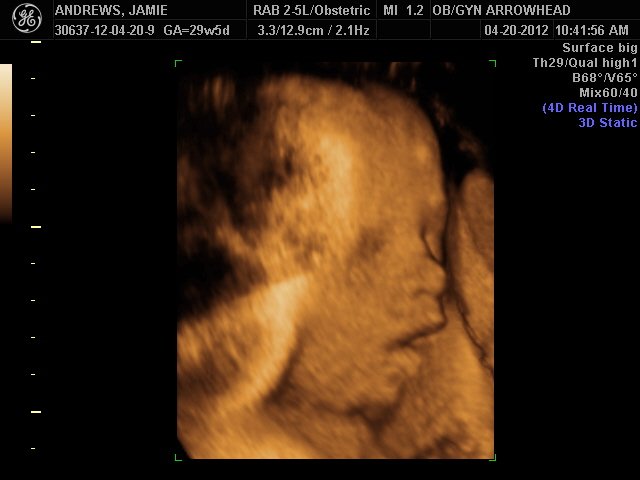

We offer complimentary 3D/4D Ultrasounds to all our OB patients around 30 weeks! The following photos are some examples of our work, shown with permission from our patients.